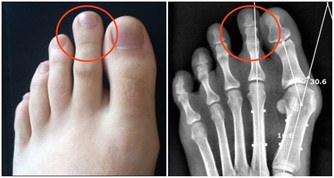

大多數草酸鈣結石原因不明。磷酸鈣和磷酸鎂銨結石與感染和梗阻有關。尿酸結石與痛風等有關。胱氨酸結石是罕見的家族性遺傳性疾病,因尿中排出大量胱氨酸所致。